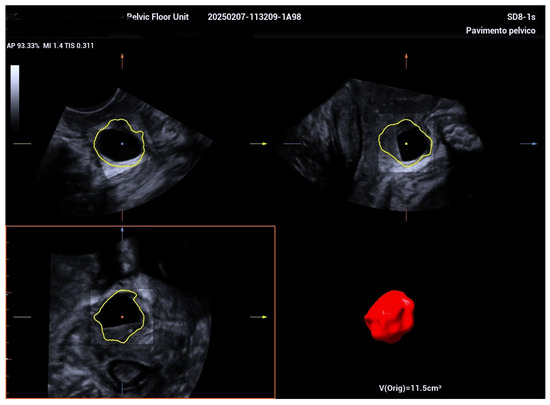

Managing Urethral Diverticulum During Pregnancy Utilizing Advanced Ultrasonographic Techniques: A Literature Review and Case Study

2. Case Report

| Jeong et al. [5] | Suprapubic pain, purulent discharge, leakage | 5.5 cm | TVUS, TPUS, 3D ultrasound at 34 weeks | Antibiotics; aspiration considered | Planned vaginal delivery | Postpartum diverticulectomy |